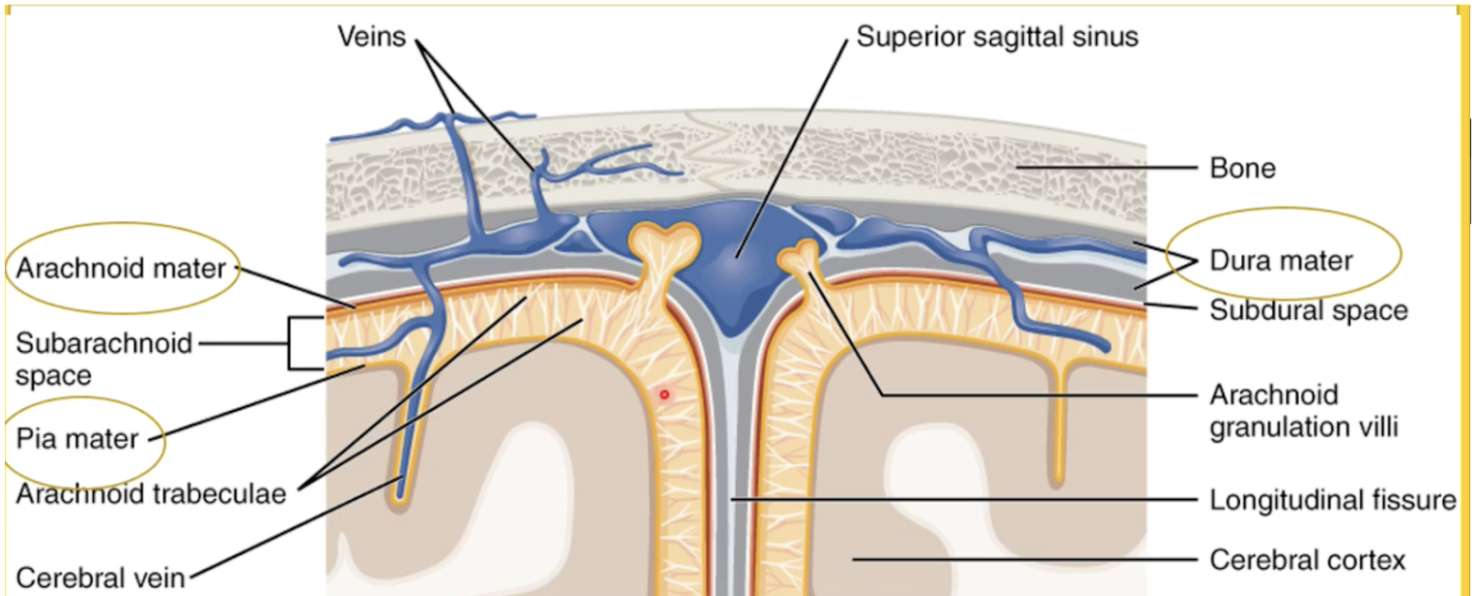

List the protective layers of the brain from outer to inner.

(1)Skin

(2)Cranial bone

(3) Cranial meninges

(4)Cerebrospinal Fluid (CSF)

What are the three layers of the Cranial Meninges (thickest to thinnest)?

Dura Mater,Arachnoid Mater, Pia Mater

Which meningeal layer is thick, fibrous, provides physical protection, and is where brain bleeds occur when damaged?

The Dura Mater.

Which meningeal layer is thin, fibrous, looks like a web, and contains the cerebrospinal fluid (CSF)?

The Arachnoid mater

Where is the CSF located relative to the Arachnoid mater?

In the Subarachnoid space

Which meningeal layer is very thin, the deepest layer, and follows all the grooves of the brain?

The Pia mater.

How is excess CSF drained?

flows into the arachnoid villi where it is drained into dural venousus sinus with the blood